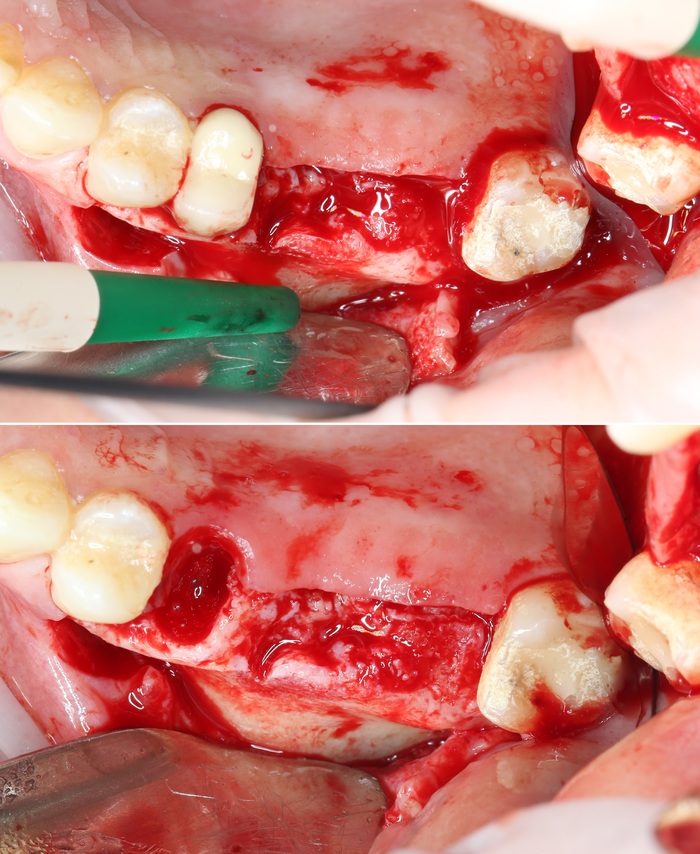

Наконечником вырезается костная стенка и кладется в чашку с физ. раствором.

Хорошо видно слизистую оболочку, которая выстилает пазуху изнутри.

А это та самая костная стенка (толщина):

На очереди сам синус-лифтинг.

Ошибочно полагать, что синус-лифтинг — это операция «В» верхнечелюстной (Гайморовой) пазухе. На самом же деле манипуляция проводится «ПОД» ней.

Как мы уже выяснили, пазуха — это полость на верхней челюсти, пустота, если хотите, которая выстлана изнутри тонкой слизистой оболочкой. Местно проводится отслоение слизистой оболочки от костной ткани, а в сформировавшееся пространство между дном пазухи и слизистой оболочкой, как в конверт, помещается костный материал.

Данная манипуляция проводится при помощи специальных кюрет, рабочая часть которых загнута под разными углами. Это позволяет произвести отслоение слизистой оболочки в любых труднодоступных местах: